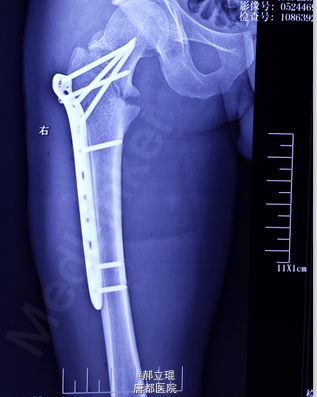

股骨颈基底部

拍X光片,显示股骨颈基底部骨折。

各项指标都正常后,施行股骨颈基底部手术。